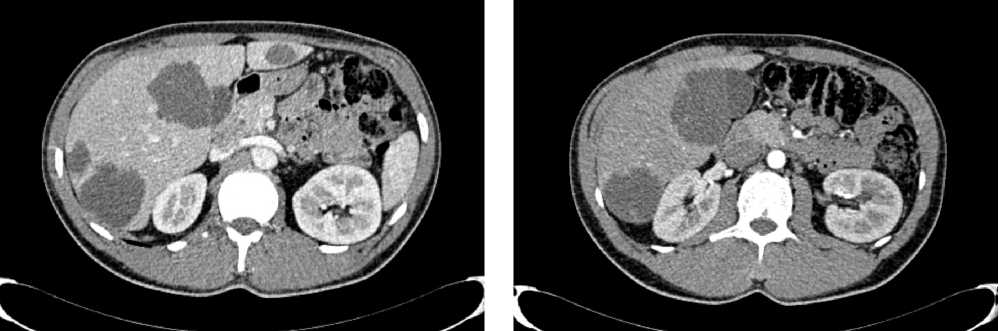

С июля 2022 г. у пациента отмечено появление эпизодов субфебрильной лихорадки. По результатам КТ органов брюшной полости от 08.2022 г. в проекции селезенки выявлена неоднородная инфильтрация с включениями, воздушной полостью в структуре, с тенденцией к отграничению и с распространением в параколическую клетчатку размерами 125 × 98 × 96 мм. Опухоль распространяется на большую кривизну желудка, вызывая утолщение стенки толщиной до 37 мм. По передней брюшной стенке справа отмечается округлое образование размерами 10 × 9 мм (рис. 5).

Рис. 5. Результаты компьютерной томографии органов брюшной полости у пациента 62 лет с диагнозом метастатический колоректальный рак с признаками микросателлитной нестабильности (август 2022 г., до лечения)

Fig. 5. Results of a CT scan of the abdomen of a 62-year-old patient with metastatic MSI-H colorectal cancer (August 2022, before treatment)

По результатам иммуногистохимического и молекулярно-генетического исследований, выявлены признаки dMMR/MSI-H (не экспрессируется MLH1) и мутация G12D в 12 кодоне гена KRAS.

По решению мультидисциплинарной комиссии, с учетом выявленного прогрессирования заболевания, его распространенности (массивный опухолевый конгломерат в левом подреберье, вовлекающий близлежащие петли кишки и дистальные отделы желудка, поджелудочную железу), ограничивающей проведение хирургического лечения, биологического статуса опухоли (dMMR/MSI-H), соматического статуса пациента ECOG-2 (обусловлен болевым синдромом), рекомендована 1 линия иммунотерапии пембролизумабом.

С 12.10.2022 пациенту выполнено 15 введений пембролизумаба с промежуточным эффектом частичный регресс.

По результатам КТ органов брюшной полости (ОБП) от 08.2023, поддиафрагмально слева сохраняется инфильтрат 79 × 46 мм, распространяется на большую кривизну желудка, брюшину, диафрагму слева и по левому фланку брюшной полости. Желудок деформирован, стенки утолщены. Парагастральная и внутрибрюшинная клетчатка слева инфильтрирована. По брюшине сохраняются образования. Эффект лечения оценен как частичный регресс (рис. 6).

Рис. 6. Частичный регресс, по данным компьютерной томографии органов брюшной полости, на фоне иммунотерапии пембролизумабом у пациента 63 лет с диагнозом метастатический колоректальный рак с признаками микросателлитной нестабильности (август 2023 г.)

Fig. 6. Partial regression according to abdominal CT scan during immunotherapy with pembrolizumab in a 63-year-old patient with metastatic MSI-H colorectal cancer (August 2023)